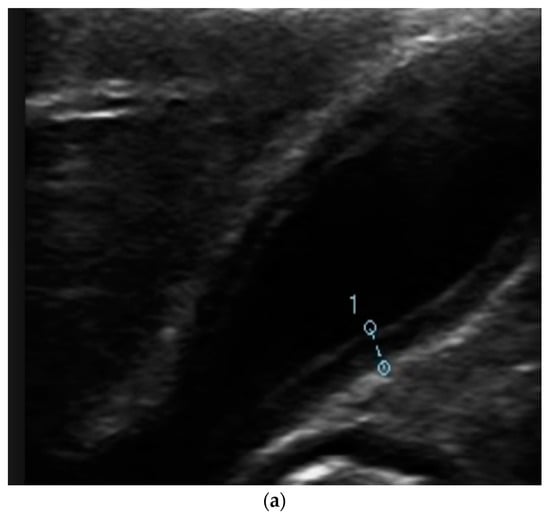

Complications

5. Diagnosis